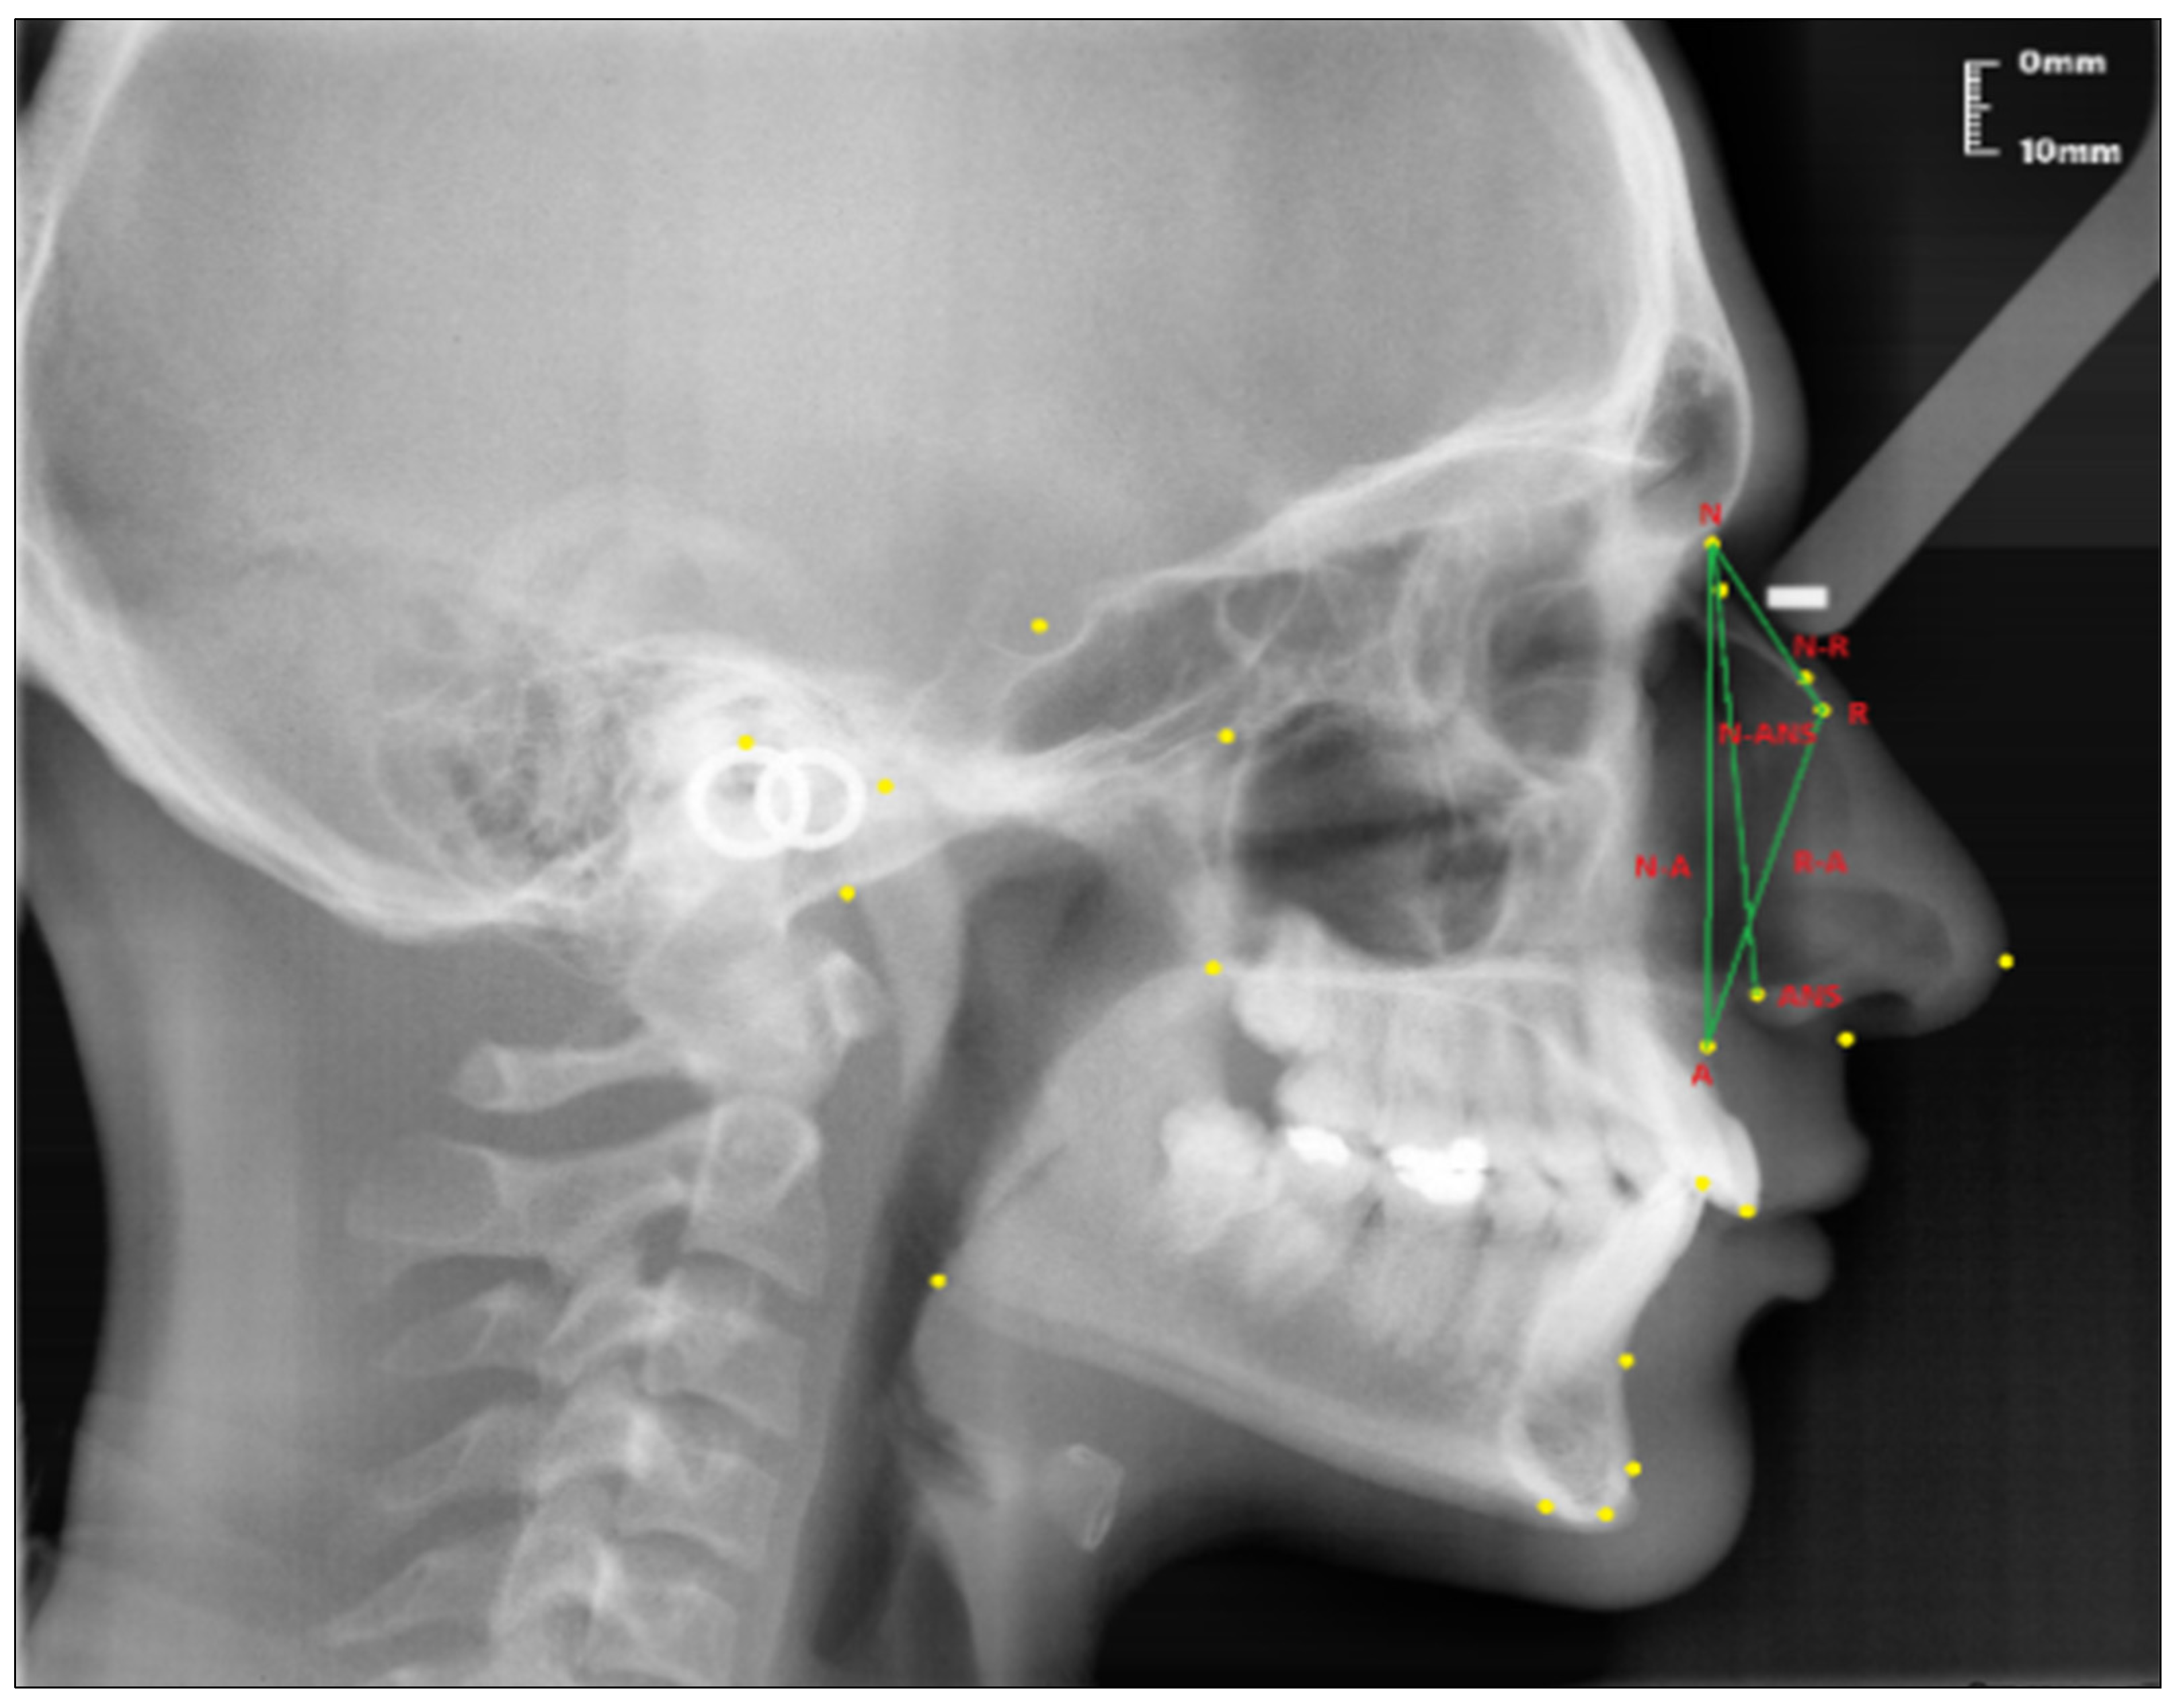

Linear measurements (see Figure 2):

Figure 2.

Linear measurements of the nasal profile used in the study.

- Nasion-Rhinion (N-R); the distance between the nasion and the rhinion points.

- Nasion-Anterior nasal spina (N-ANS); the distance between the nasion and the anterior nasal spina points.

- Rhinion-Subspinale (R-A); the distance between the rhinion and the subspinale points.

- Nasion-Subspinale (N-A); the distance between the nasion and the subspinale points.